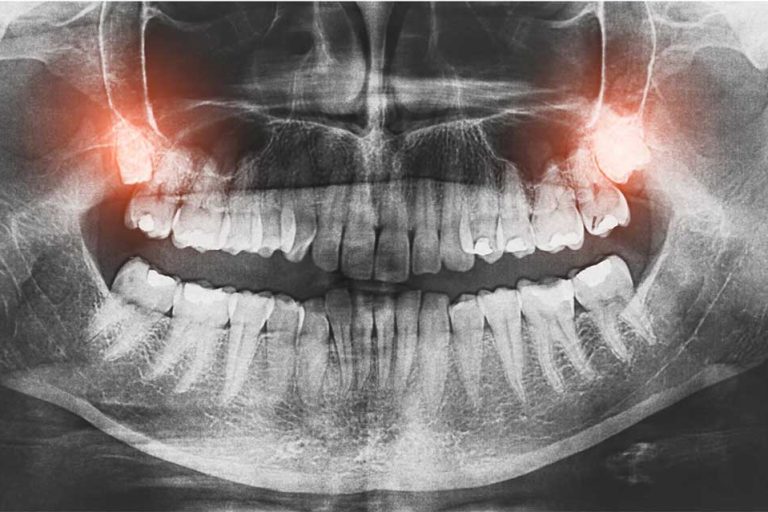

Teeth can become weak if they are heavily filled or if you have a large decaying lesion in them. By the time you have taken away the decay, you are sometimes left with thin parts of the tooth and the studies show that these are likely to fracture at some stage. Every time you’re eating it’s like someone’s putting a hammer to the tooth and this can cause the thin bits to crack. If you’re a grinder then it’s way more likely to fracture. The job of a crown is to act like a helmet, it protects the tooth from cracking. Now you may think that it’s worth leaving it and when it does crack, to crown it then. The problem is that you never know how much of it will crack. If it’s a large crack then the tooth may not be salvageable, and you may need to have it taken out. That’s why it’s better to crown them right from the start so you can increase the longevity of the tooth.

- How much tooth structure you have. This is probably the single most important factor, if you have a good amount of tooth structure to begin with the crown should last a long time. Conversely, if you have a very broken-down tooth, and there is not much of the tooth to bond to, then the crown may de-bond in the future. If the tooth is very weak after the crown preparation, the tooth may fracture and hence the crown de-bonds.